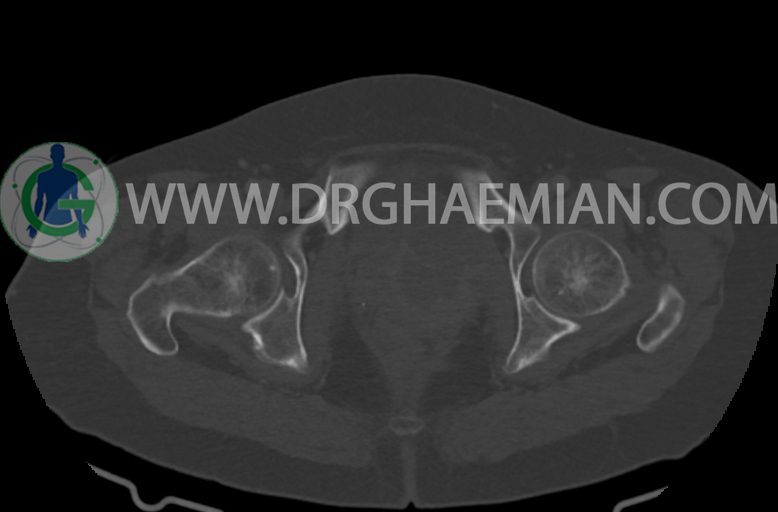

در سی تی اسکن اسپیرال ریه ها و مدیاستن ، شکم و لگن با و بدون کنتراست وریدی (مولتی دیدکتور 16 با مقاطع ظریف و بازسازی کرونال):

–ساختار Cystic multiseptate همراه با Enhancing thick septation به ابعاد 79x62mm در

لگن دیده می شود که در درجه اول مطرح کننده ی ضایعات نئوپلاستیک تخمدانی نظیر mucinous cyst adenocarcinoma است.

–شواهد هیسترکتومی

–ضایعه ی mass like هیپردنس- هتروژن به قطر 42mm در سمت راست لگن